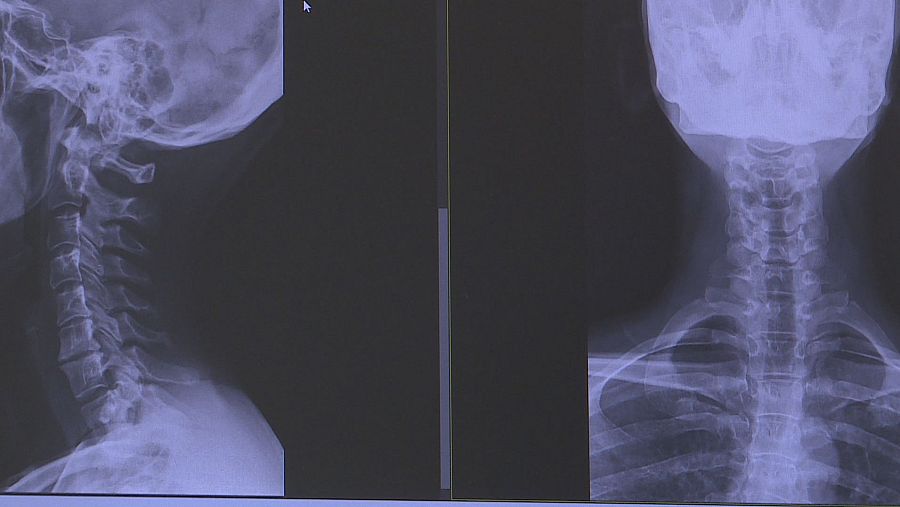

Víctor del Pozo es fisioterapeuta en el Hospital QuirónSalud de Toledo y explica que cuando una persona utiliza el teléfono móvil o la tablet, tiende a inclinar el cuello hacia abajo. “De ahí que cuando se excede su uso, el dolor se localiza, sobre todo, en la parte baja y posterior de la cabeza, en la zona cervical, en los trapecios e incluso en la inserción en el cráneo”. También añade que incluso se pueden ver perjudicadas las vértebras, porque si sufren mucho estrés mecánico, podría derivar en problemas más graves.

Si inclinamos la cabeza más allá de 30 grados durante mucho tiempo, multiplicamos seis veces su peso

“Nuestra cabeza pesa entre 4 o 5 kilos. Pero si la inclinamos más allá de 30 grados durante mucho tiempo, multiplicamos ese peso por seis”, aclara el doctor Nahuel Barquero, especialista de la Unidad de Columna del Servicio de Cirugía Ortopédica y Traumatología del complejo hospitalario QuirónSalud en la capital de Castilla-La Mancha. Además, puntualiza que “cuando estamos leyendo o viendo un video en un dispositivo, la inclinación es de unos 60 grados. Al hacerlo, estamos sobrecargando en exceso toda la musculatura y el aparato esquelético del cuello”.